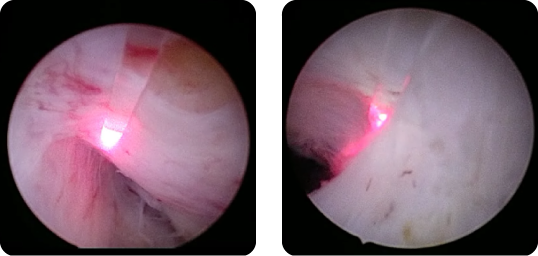

ECIRS

術中外観

Pass the ball

リソクラストによる砕石